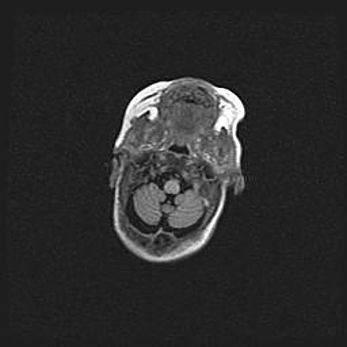

Аномалия Денди-Уокера. Признаки гипоплазии мозолистого тела.

Возраст: 5 месяцев 3 дня

Вес: 5550 г

Пол: мужской

Окружность головы: 39 см

Срок гестации: 40 недель

Аномалия Денди-Уокера – это порок развития головного мозга, для которого характерна триада симптомов: гипотрофия или аплазия червя мозжечка и/или полушарий мозжечка, расширение четвёртого желудочка с формированием ликворной кисты задней черепной ямки, гипертензионная гидроцефалия различной степени.

Гипоплазия мозолистого тела относится к дефектам внутриутробного этапа развития мозговой ткани, возникающим в процессе закладки структур головного мозга, что происходит на начальных этапах развития эмбриона.